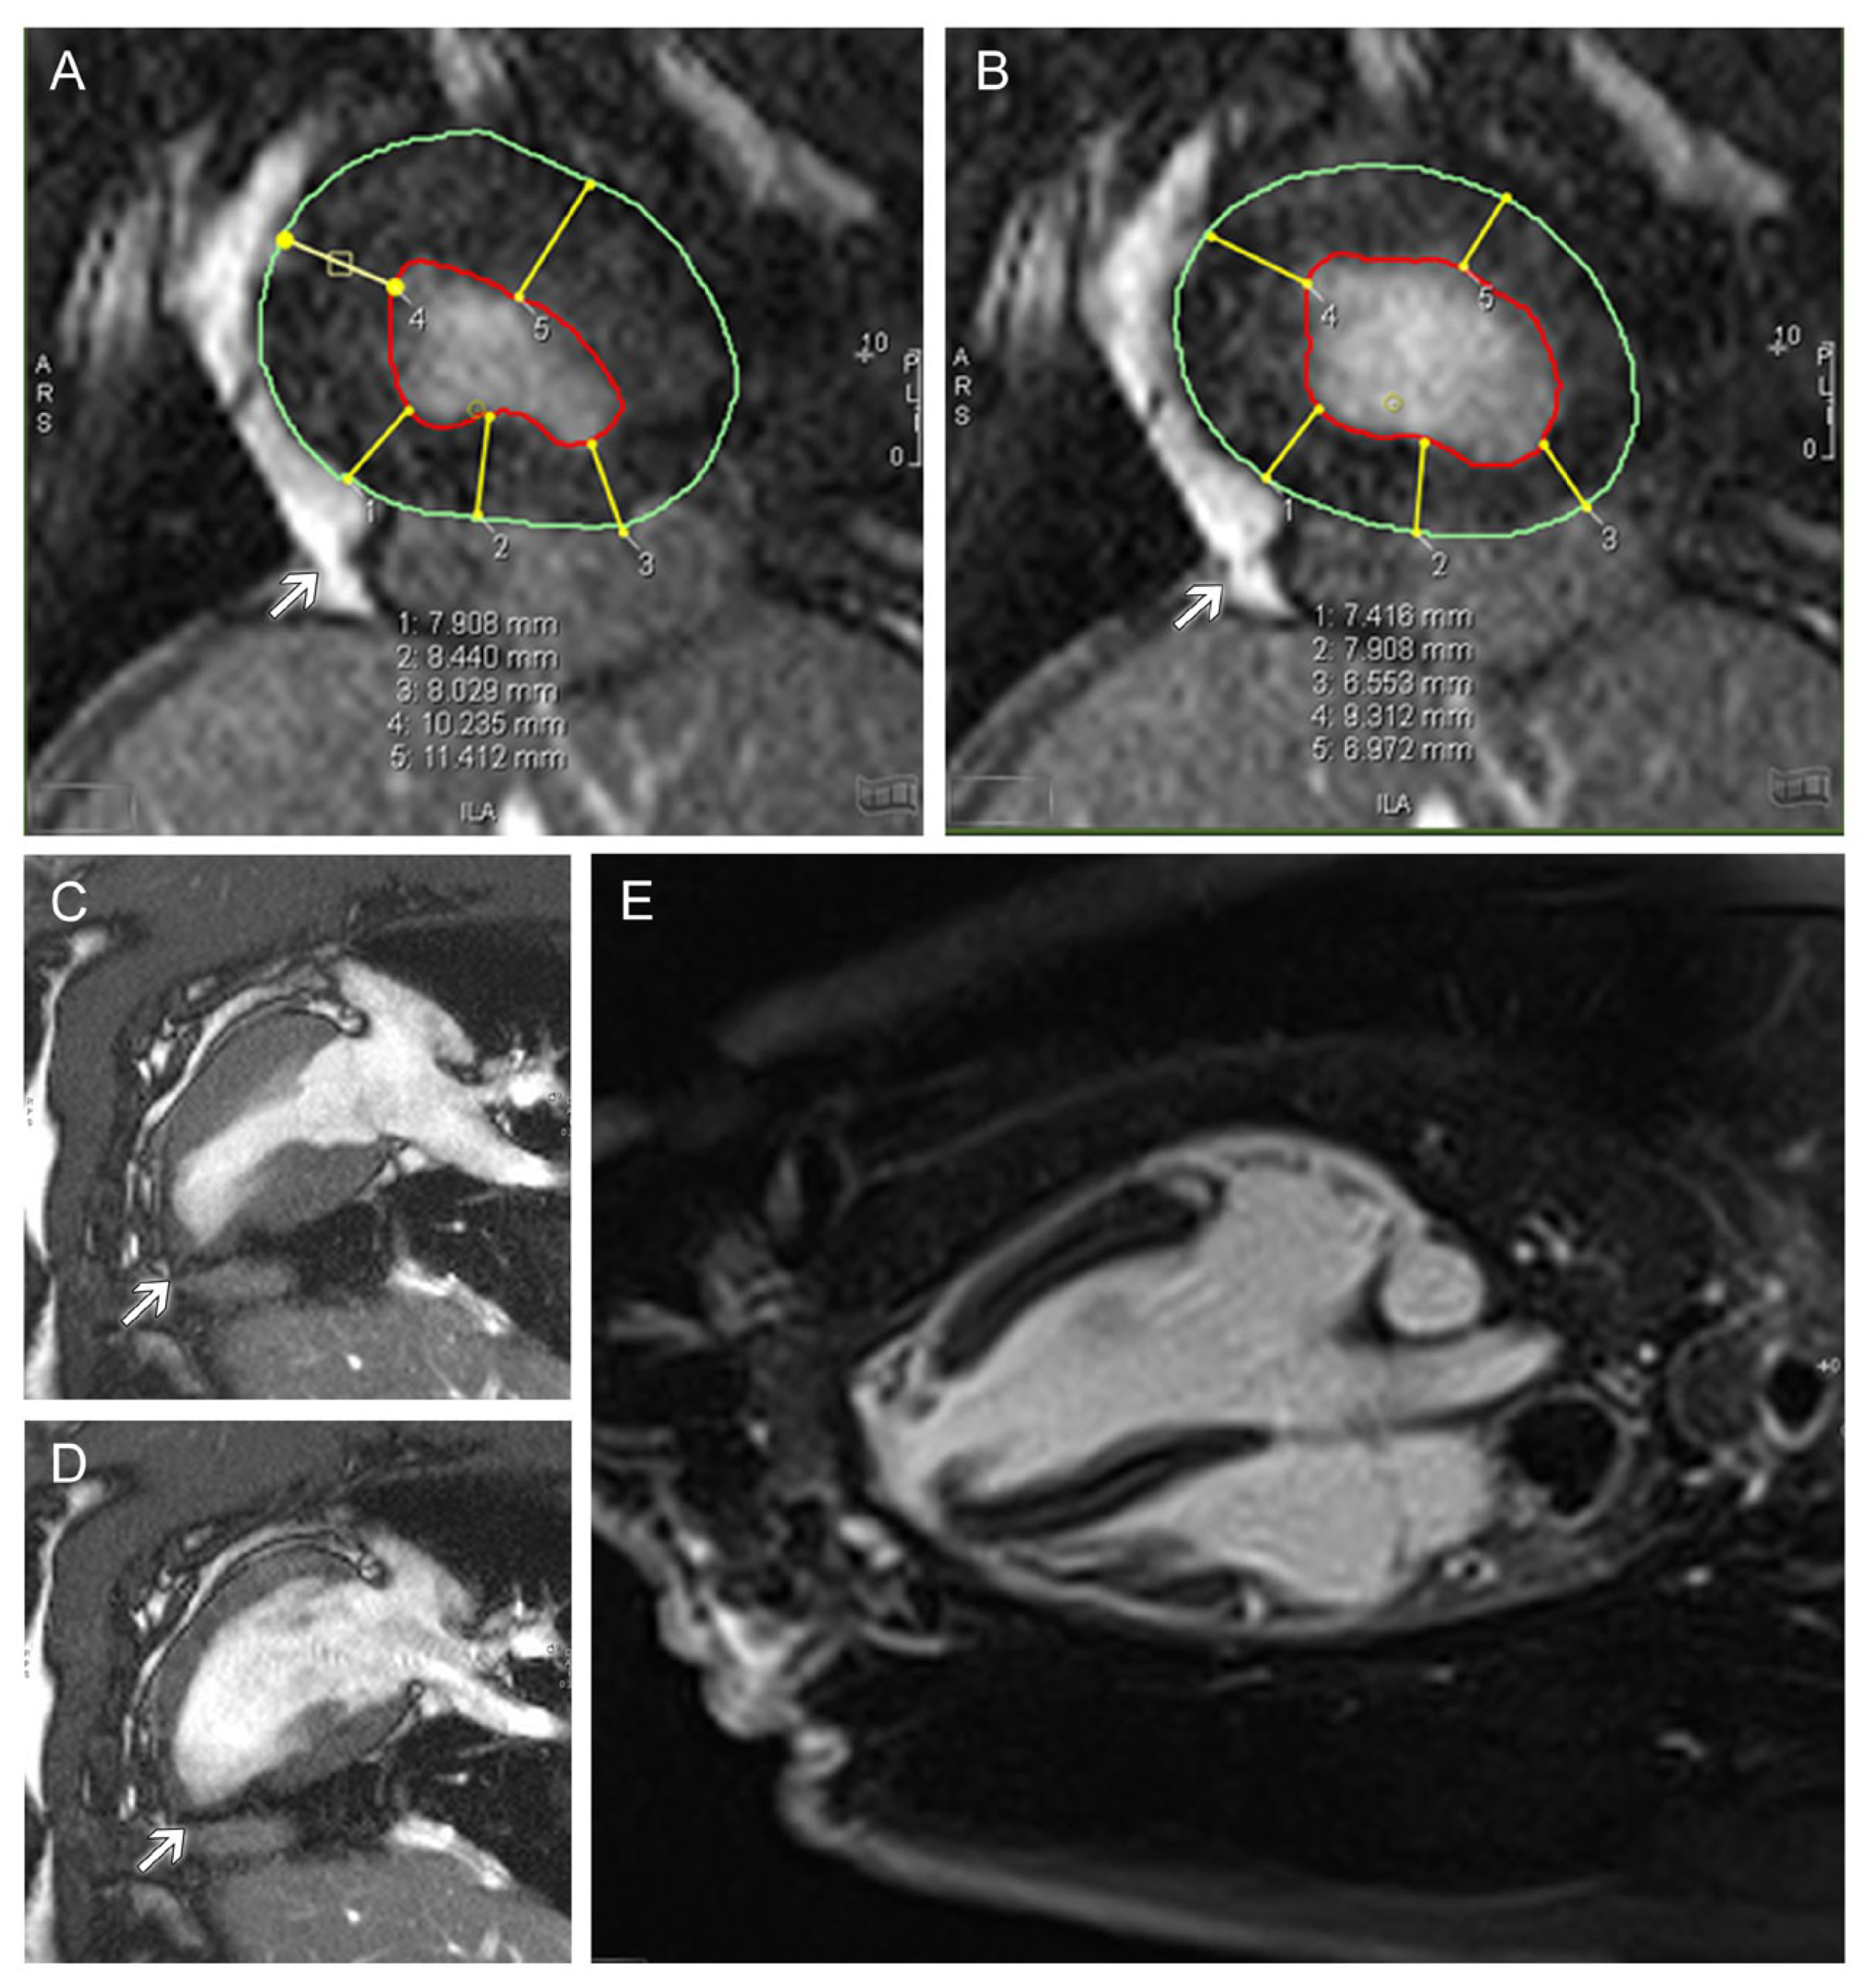

Overall, the left ventricles were of normal size. The area of the implanted patch and the surrounding zone of the myocardium were functionally stable without rupture or aneurysm of the tissue (Figure 7C,D). Compared with the properly contracting healthy myocardium on the opposite side, akinesia was detected in the central patch area (Figure 7C,D) and hypokinesia in the border zone of the patch. A slight increase in wall thickness was seen in the edge region of the patch during the end-systolic and end-diastolic phases (Figure 7A,B), which was less prominent than in the native, opposite side of the ventricle (Figure 7C,D). Overall, the patch area demonstrated an inhomogeneously delayed enhancement of the contrast agent, indicating a stabilizing fibrosis (Figure 7E).

Figure 7.

(A + B): MRI measurement of end-systolic (A) and end-diastolic (B) wall thickness of left ventricular myocardium. (C + D): MRI of the left ventricle as a two-chamber view during systole (C) and diastole (D) showing akinesia of the central region of the decellularized pericardium and stomach patch as well as hypokinesia of the peripheral areas. (E): MRI of the left ventricle as a four-chamber view close to the apex cordis with delayed enhancement indicating fibrosis (light grey) in the patch area in contrast to native myocardium (dark grey). Arrows indicate the area of the implanted stomach tissue. The end-diastolic volume of the left ventricle, including the gastric patch, was in a normal range compared with a healthy control animal with an average left ventricular ejection fraction of 54%. The volumes and function values of the right ventricle were also in the normal range (RV-EDV: 40 mL; RV-ESV: 18 mL; RV-SV: 23 mL; RV-EF: 56%; muscle mass: 20 g).